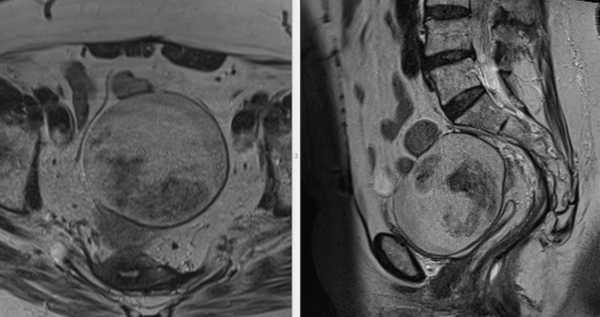

МРТ малого таза. В структуре яичника отмечается крупная киста с толстыми стенками, с неоднородным (белковым) содержимым, без перегородок и папиллярных разрастаний.

Отмечается повышение интенсивности МР-сигнала от содержимого кисты на ДВИ с признаками выраженного снижения на ИКД (в,г) - МР-признаки воспалительного (гнойного) содержимого.